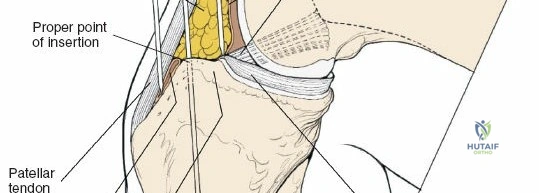

- Proximal Tibia: The preferred entry point for tibial nails lies in the proximal tibia, typically between the anterior tibial spine and the lateral edge of the patellar tendon. The infrapatellar fat pad (Hoffa's fat pad) must be navigated. Careful attention to the articular surface is paramount to avoid iatrogenic damage to the tibial plateau. The patellar tendon can be split or approached paratendinously, with long-term studies showing no significant difference in knee pain.

- Incision: A short, vertical incision (typically 2-3 cm) is made over the proximal tibia. This is commonly a midline incision, but some surgeons prefer a parapatellar approach.

The incision should be adequate to allow clear access to the entry point and accommodate the targeting jig. The patellar tendon can be carefully split longitudinally or approached paramedially (medial or lateral to the tendon). - Entry Point Determination: The ideal entry point is crucial for proper nail alignment and preventing iatrogenic damage. It is typically located on the anterior cortex of the tibia, just medial to the lateral edge of the patellar tendon, distal to the articular surface of the tibial plateau.

- Fluoroscopic Guidance: Use an Awl or K-wire under AP and lateral fluoroscopy to confirm the entry point. The AP view should show the wire positioned to align with the central axis of the medullary canal. The lateral view should show the wire in line with the anterior cortex, avoiding a posterior entry which can damage the posterior cortex and lead to malalignment.

Fluoroscopy is continuously used to monitor nail progression and ensure it passes smoothly across the fracture site. Any resistance should prompt reassessment of reduction and guide wire position. - Final Seating: The nail is advanced until its proximal end is flush with or slightly recessed below the articular surface of the tibial plateau. Excessive prominence can lead to anterior knee pain.